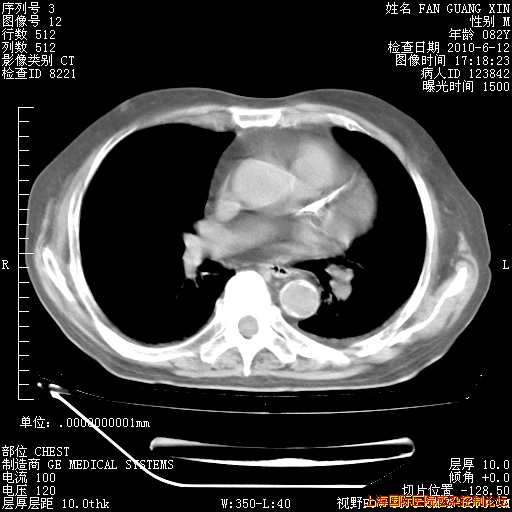

6月12日肺窗

6月12日纵膈窗